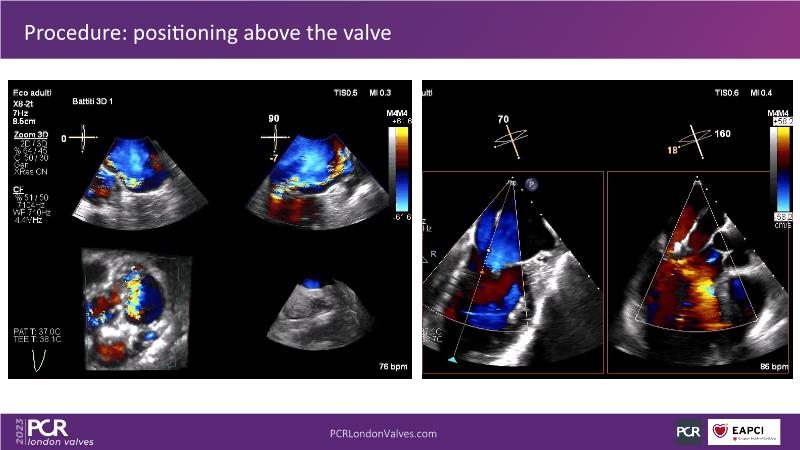

This session explores the features of the PASCAL Precision and the EVOQUE tricuspid replacement systems through simulators and case presentations, while a panel of experts discuss the technology, witnessing live demonstrations of treating mitral and tricuspid regurgitation patients.

- To learn about the differentiating features of the PASCAL Precision system showcased in a series of simulators alongside case presentations

- To interact with a panel of experts discussing the PASCAL Precision system technology and showcasing, live, its different key features in action and how they help treat mitral regurgitation and tricuspid regurgitation patients